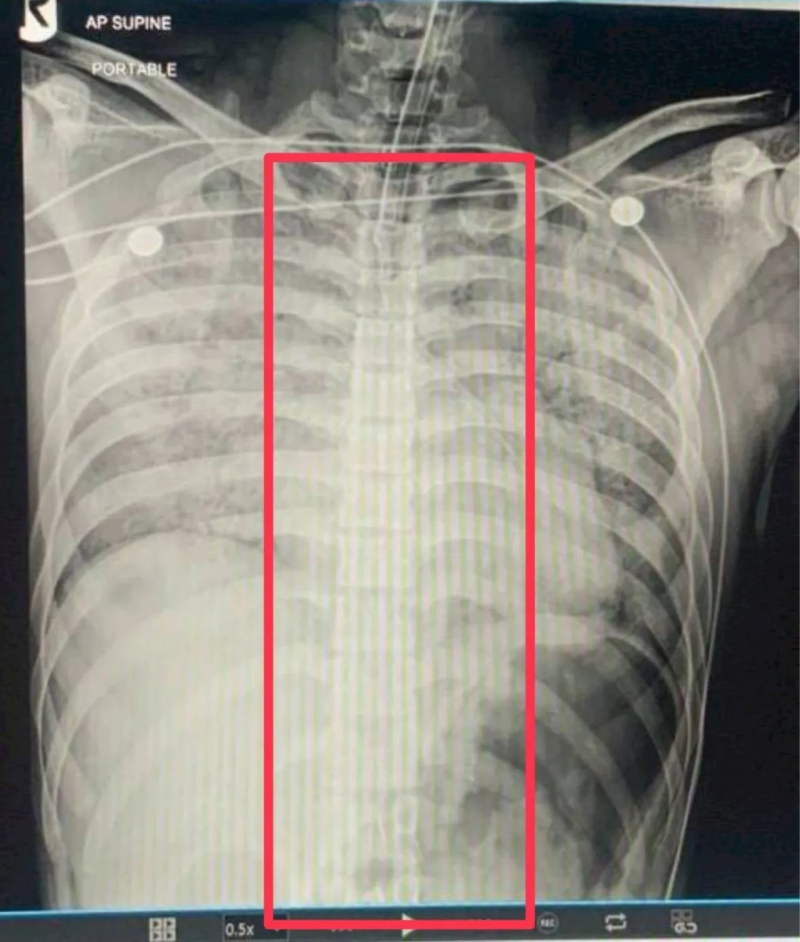

โดยส่วนตัวผมไม่ทราบว่า ช้อนมาได้ยังไง เท่าที่ทราบจากการผ่าพิสูจน์จะมีฟิล์มเอกซเรย์ของทางโรงพยาบาล ไม่ปรากฏ ช้อน อยู่ในร่างกายของผู้เสียชีวิต และมีการนัดหมายกับทางญาติ และหน่วยงานที่เกี่ยวข้อง นำรูปถ่ายและคลิปต่างๆ ให้ญาติดู และเดินเข้าไปดูด้านใน ซึ่งขณะนั้นญาติไม่ติดใจอะไร เข้าใจว่าน้องเสียชีวิตด้วยโรคส่วนตัว